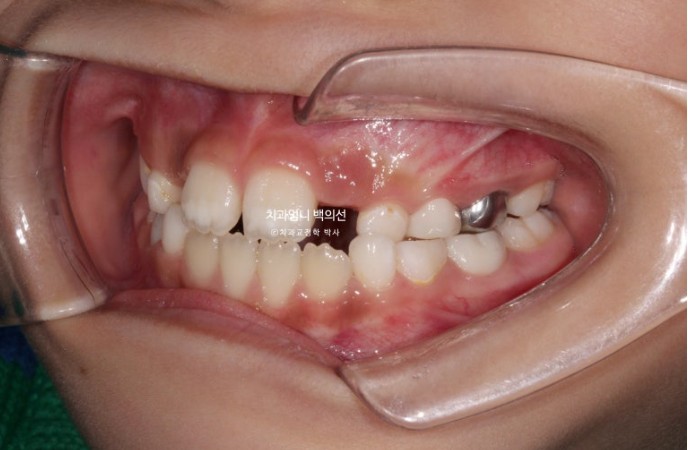

윗니가 아랫니를 덮지 못하는 절단교합입니다.

측절치와 송곳니날 자리가 부족해서 악궁확장도 필요한 상황입니다.

인비절라인 퍼스트로 치료에 들어갔고 악궁확장으로 영구치 맹출공간 회복, 공간 분배, 반대교합 해소로 교합간섭 해소에 의한 아래턱 위치 개선으로 비대칭 해결 등을 목표로 치료에 들어갔습니다.

악궁확장으로 파란 화살표 반대교합이 해소가 되면서 교합간섭이 사라졌습니다.

아래 붙어있는 메탈 고리는 고무줄 거는 고리입니다.

악궁확장으로 넓어진 악궁 덕분에 공간이 좁아 못 나오던 측절치도 잘 나오고 있습니다.